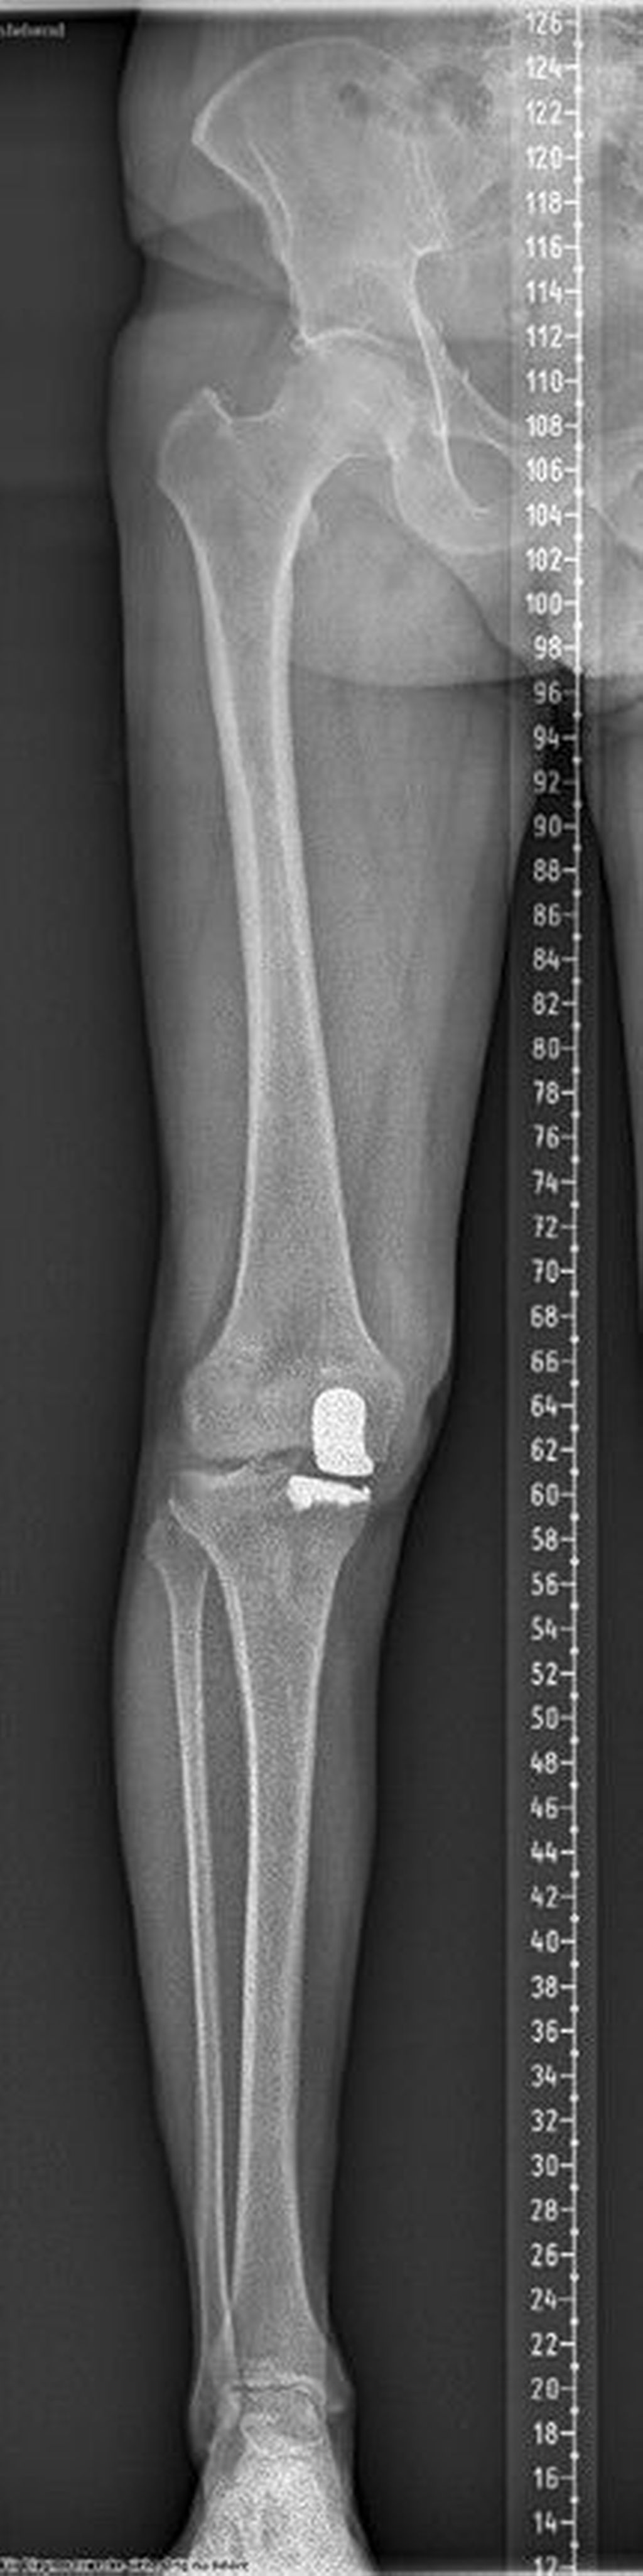

Abb. 3: Postoperatives Bild nach Implantation einer medialen Hemischlittenprothese

Ein 62-jähriger Patient stellte sich im März 2025 mit belastungsabhängigen Knieschmerzen rechts vor. Im MRT zeigte sich eine Läsion des medialen Meniskus, sodass in Zusammenschau mit dem positiven Meniskuszeichen in der klinischen Untersuchung eine partielle Meniskektomie durchgeführt wurde. Die postoperative Phase verlief zunächst unauffällig. Der Patient berichtete über ein beschwerdefreies Intervall von rund sieben Wochen. Anschließend entwickelten sich jedoch erneut zunehmende Schmerzen im rechten Kniegelenk, die eine erneute Vorstellung in der Spezialambulanz erforderlich machten. Er berichtete vor allem über belastungsabhängige Schmerzen im Bereich des medialen Kniegelenks. Daraufhin wurde ein Ganzbeinröntgen zur Beurteilung der Beinachse durchgeführt, hier zeigte sich eine varische Beinachse mit 5 Grad Varus (Abb.1). In der ergänzend durchgeführten MRT-Untersuchung konnte medialseitig eine ausgeprägte Nekrosezone am medialen Femurkondyl nachgewiesen werden (Abb.2). Schlussendlich wurde aufgrund dieses Befundes die Indikation zur Implantation einer medialen Hemischlittenprothese rechts gestellt, die schließlich im August 2025 komplikationslos durchgeführt wurde (Abb.3+4).